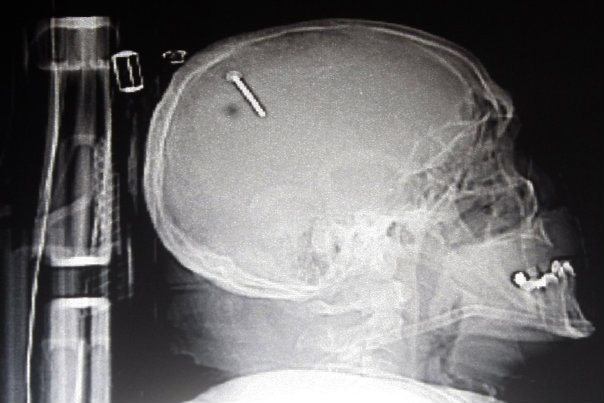

2. Snimka pokazuje čavao u glavi Georgea Chandlera iz savezne države Kansas. Chandler i prijatelj radili su na projektu kada je pištolj za ispaljivanjE čavala iznenada opalio. Chandler je kasnije izjavio kako nije znao gdje je metak završio ali je osjetio lagani ubod na vrhu glave.